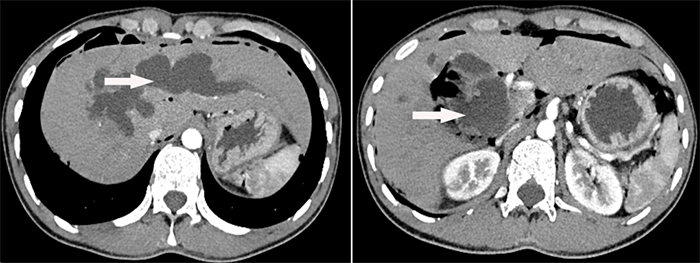

腹部增強(qiáng)CT顯示肝內(nèi)外膽管囊狀病變

為盡快解除病痛,早日回歸正常生活,主管醫(yī)生與患者及患者家屬就該疾病進(jìn)行了詳細(xì)溝通和交流,進(jìn)行了腹部增強(qiáng)CT、MRCP等相關(guān)檢查,明確了病因和疾病位置,患者診斷為先天性膽管擴(kuò)張癥(Ⅳ型)、肝內(nèi)外膽管結(jié)石,并進(jìn)行了住院治療。

MRCP顯示肝內(nèi)外膽管囊狀病變及膽管結(jié)石

經(jīng)科室內(nèi)全體醫(yī)生討論,先天性膽管擴(kuò)張癥的并發(fā)癥發(fā)生率高達(dá)20~60%,且有一定癌變率,癌變率隨患者年齡增大而遞增。該患者病變廣泛并波及肝內(nèi)外膽管,除肝外膽管顯著囊狀擴(kuò)張外,肝內(nèi)膽管囊狀擴(kuò)張以左半肝內(nèi)膽管顯著并膽管結(jié)石,患者手術(shù)指針明確。